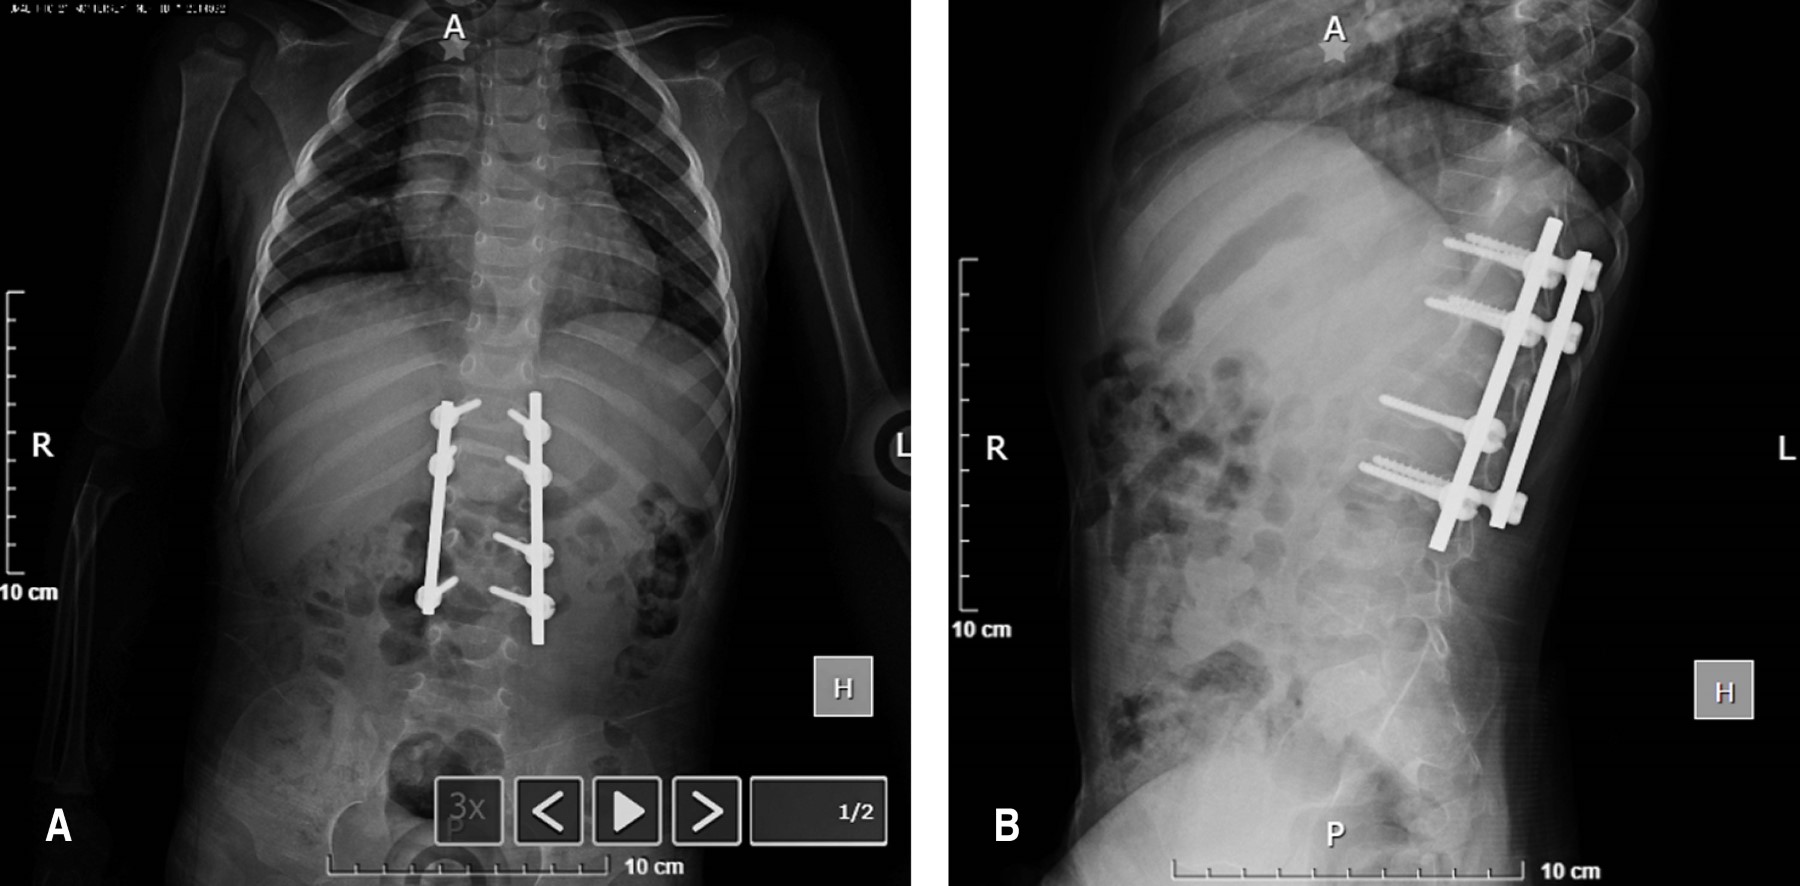

El cuadro clínico inició con síntomas inespecíficos como malestar general, irritabilidad, dolor abdominal y diarrea. Recibió tratamiento sintomático en consulta privada con una mejoría transitoria de sintomatología por una semana con antiinflamatorio no esteroideo y plan de hidratación. Posteriormente inicia recurrencia con dolor abdominal, episodios de evacuaciones diarreicas, agregando dolor axial en columna dorsolumbar, dificultad a la deambulación y aparición de una tumoración palpable dolorosa en región dorsal de aproximadamente 2 × 2 cm a nivel de T12 (Figura 1). Ante esta nueva sintomatología, el paciente fue referido a traumatología.

Ante la pobre mejoría clínica con el tratamiento conservador durante dos meses, se realizan rayos X (Figura 3) y resonancia magnética nuclear de control (Figura 4), donde se identificó permanencia del colapso vertebral, compresión de elementos neurales y extensión de la colección hacia la región prevertebral y los músculos iliopsoas bilaterales, con cambios en la intensidad de señal a nivel medular sugestivos de mielopatía en el área afectada. Se realiza intervención quirúrgica mediante instrumentación posterior toracolumbar de T12 a L3, hemilaminectomía izquierda en T12-L1 y drenaje de abscesos con obtención de 3 cc de líquido de aspecto purulento en el espacio T12-L1 y alrededor de 8 cc en la región del psoas derecho (Figura 5 y 6).

El paciente egresó del hospital a las 72 horas postquirúrgicas, cumpliendo con protocolo antimicrobiano y analgésico correspondiente, con adecuado control hemodinámico y seguimiento multidisciplinario por consulta externa con citas periódicas. Cada mes (durante los primeros seis meses) y cada dos meses (durante otros seis meses), con buena evolución: sitio quirúrgico con bordes bien afrontados, sin datos clínicos de infección o dehiscencia, con marcha independiente y no claudicante, miembros pélvicos con fuerza muscular 5/5 y sensibilidad 2/2. En la primer radiografía de control al mes de postquirúrgico se observó corrección de cifosis, material de osteosíntesis sin datos de solicitación ni aflojamiento (Figura 7). Se indicó uso de corset de toracolumbar bivalvado de manera permanente durante al menos 18 horas al día por 12 meses y mantuvo una terapia de tratamiento antifímico bajo supervisión por servicio de infectología pediátrica con buena mejoría clínica. Se plantea retirar la instrumentación en unos años para evitar secuelas en el crecimiento axial.